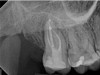

In the first case study, a young female patient was told she had a tooth (tooth No. 2, Figure 3) that should be extracted due to extensive bone loss. Using CBCT, the clinician was able to identify a large lateral canal within the palatal root. Despite the bone loss, the patient was eager to save her tooth. He offered to treat the tooth with the broad-spectrum acoustic technology. As shown in Figure 4, the preparation space was much smaller, which he was able to obturate efficiently. In addition, the small pinpoint of sealer in the middle of the palatal root indicated that the palatal lateral canal had been addressed (Figure 5). In the clinician's opinion, this area was likely the primary source of much of the bone loss.

Fig 3. Case 1: CBCT showed a large lateral canal within the palatal root (Fig 3). There was a small preparation space, which was efficiently obturated (Fig 4). A small pinpoint of sealer in the middle of the palatal root indicated that the palatal lateral canal had been addressed (Fig 5). After 5 months, CBCT demonstrated complete healing (Fig 6), notably on the distal, where probing had resolved to 2 mm. Radiographic images were taken immediately postoperatively (Fig 7) and 5 months postoperatively (Fig 8).

Figure 3